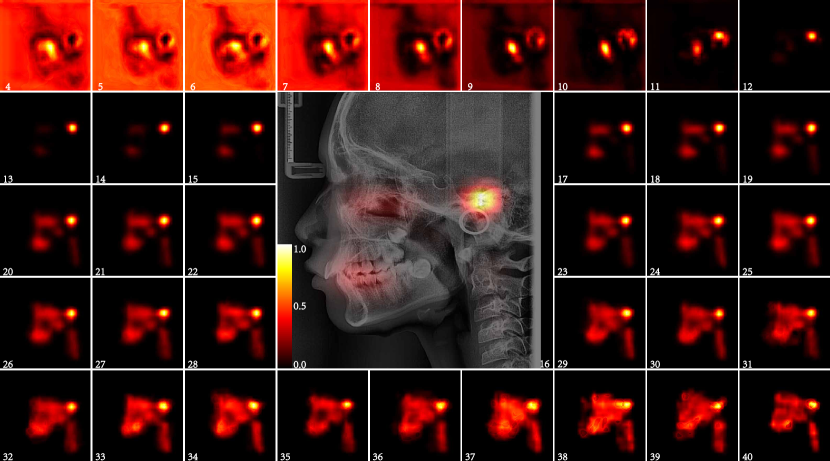

The average saliency maps of each part were shown in Fig. 12, Fig.13 and Fig.14. The salient area of each part is consistent with that of the whole LC image. The location and shape of the salient area in the heat map of each year age group showed a high degree of consistency. The salient area of teeth part were mainly teeth and periodontal tissues, especially the upper posterior teeth, this should be related to the wear of the teeth and the ageing changes of the periodontal tissue.(Fig. 12) The salient area of the craniofacial part without the teeth were mainly midface(Fig.13). Many scholars have conducted in-depth research on the aging changes of the orbit, and the volume of the orbit increases with age. The development of the maxilla is also a research hotspot, but the research on the aging of the maxilla in adults has not been involved. The saliency maps reminds us that it is necessary to conduct aging research on other organizational structures in the middle of the face. The salient area of the cervical spine part were all of cervical spines and intervertebral disc in the LC image. The morphological changes of the cervical spine are used to determining the pubertal growth spurt of adolescence[27-29]. The cervical spine was also used to infer age and gender [30-32] , but it is mainly used for children and adolescents, there is no relevant research using the cervical spine to infer the age of adults. The cervical spine consists of 7 vertebral bodies and intervertebral discs. After the development is complete, the structural changes of the cervical spine begin in middle age, but sometimes earlier[33]. I ntervertebral disc degeneration begins at adolescence, and as it progresses, it can also leads to morphological alterations of the vertebral bodies. Cervical lordosis increased with age[34]. These changes are difficult to use by traditional methods of inferring age.

In this study, we found that the accuracy of age estimation of cervical part is the highest among all parts in the 26-40 age group, which indicates that cervical region should be highly concerned, which is worthy of further study.